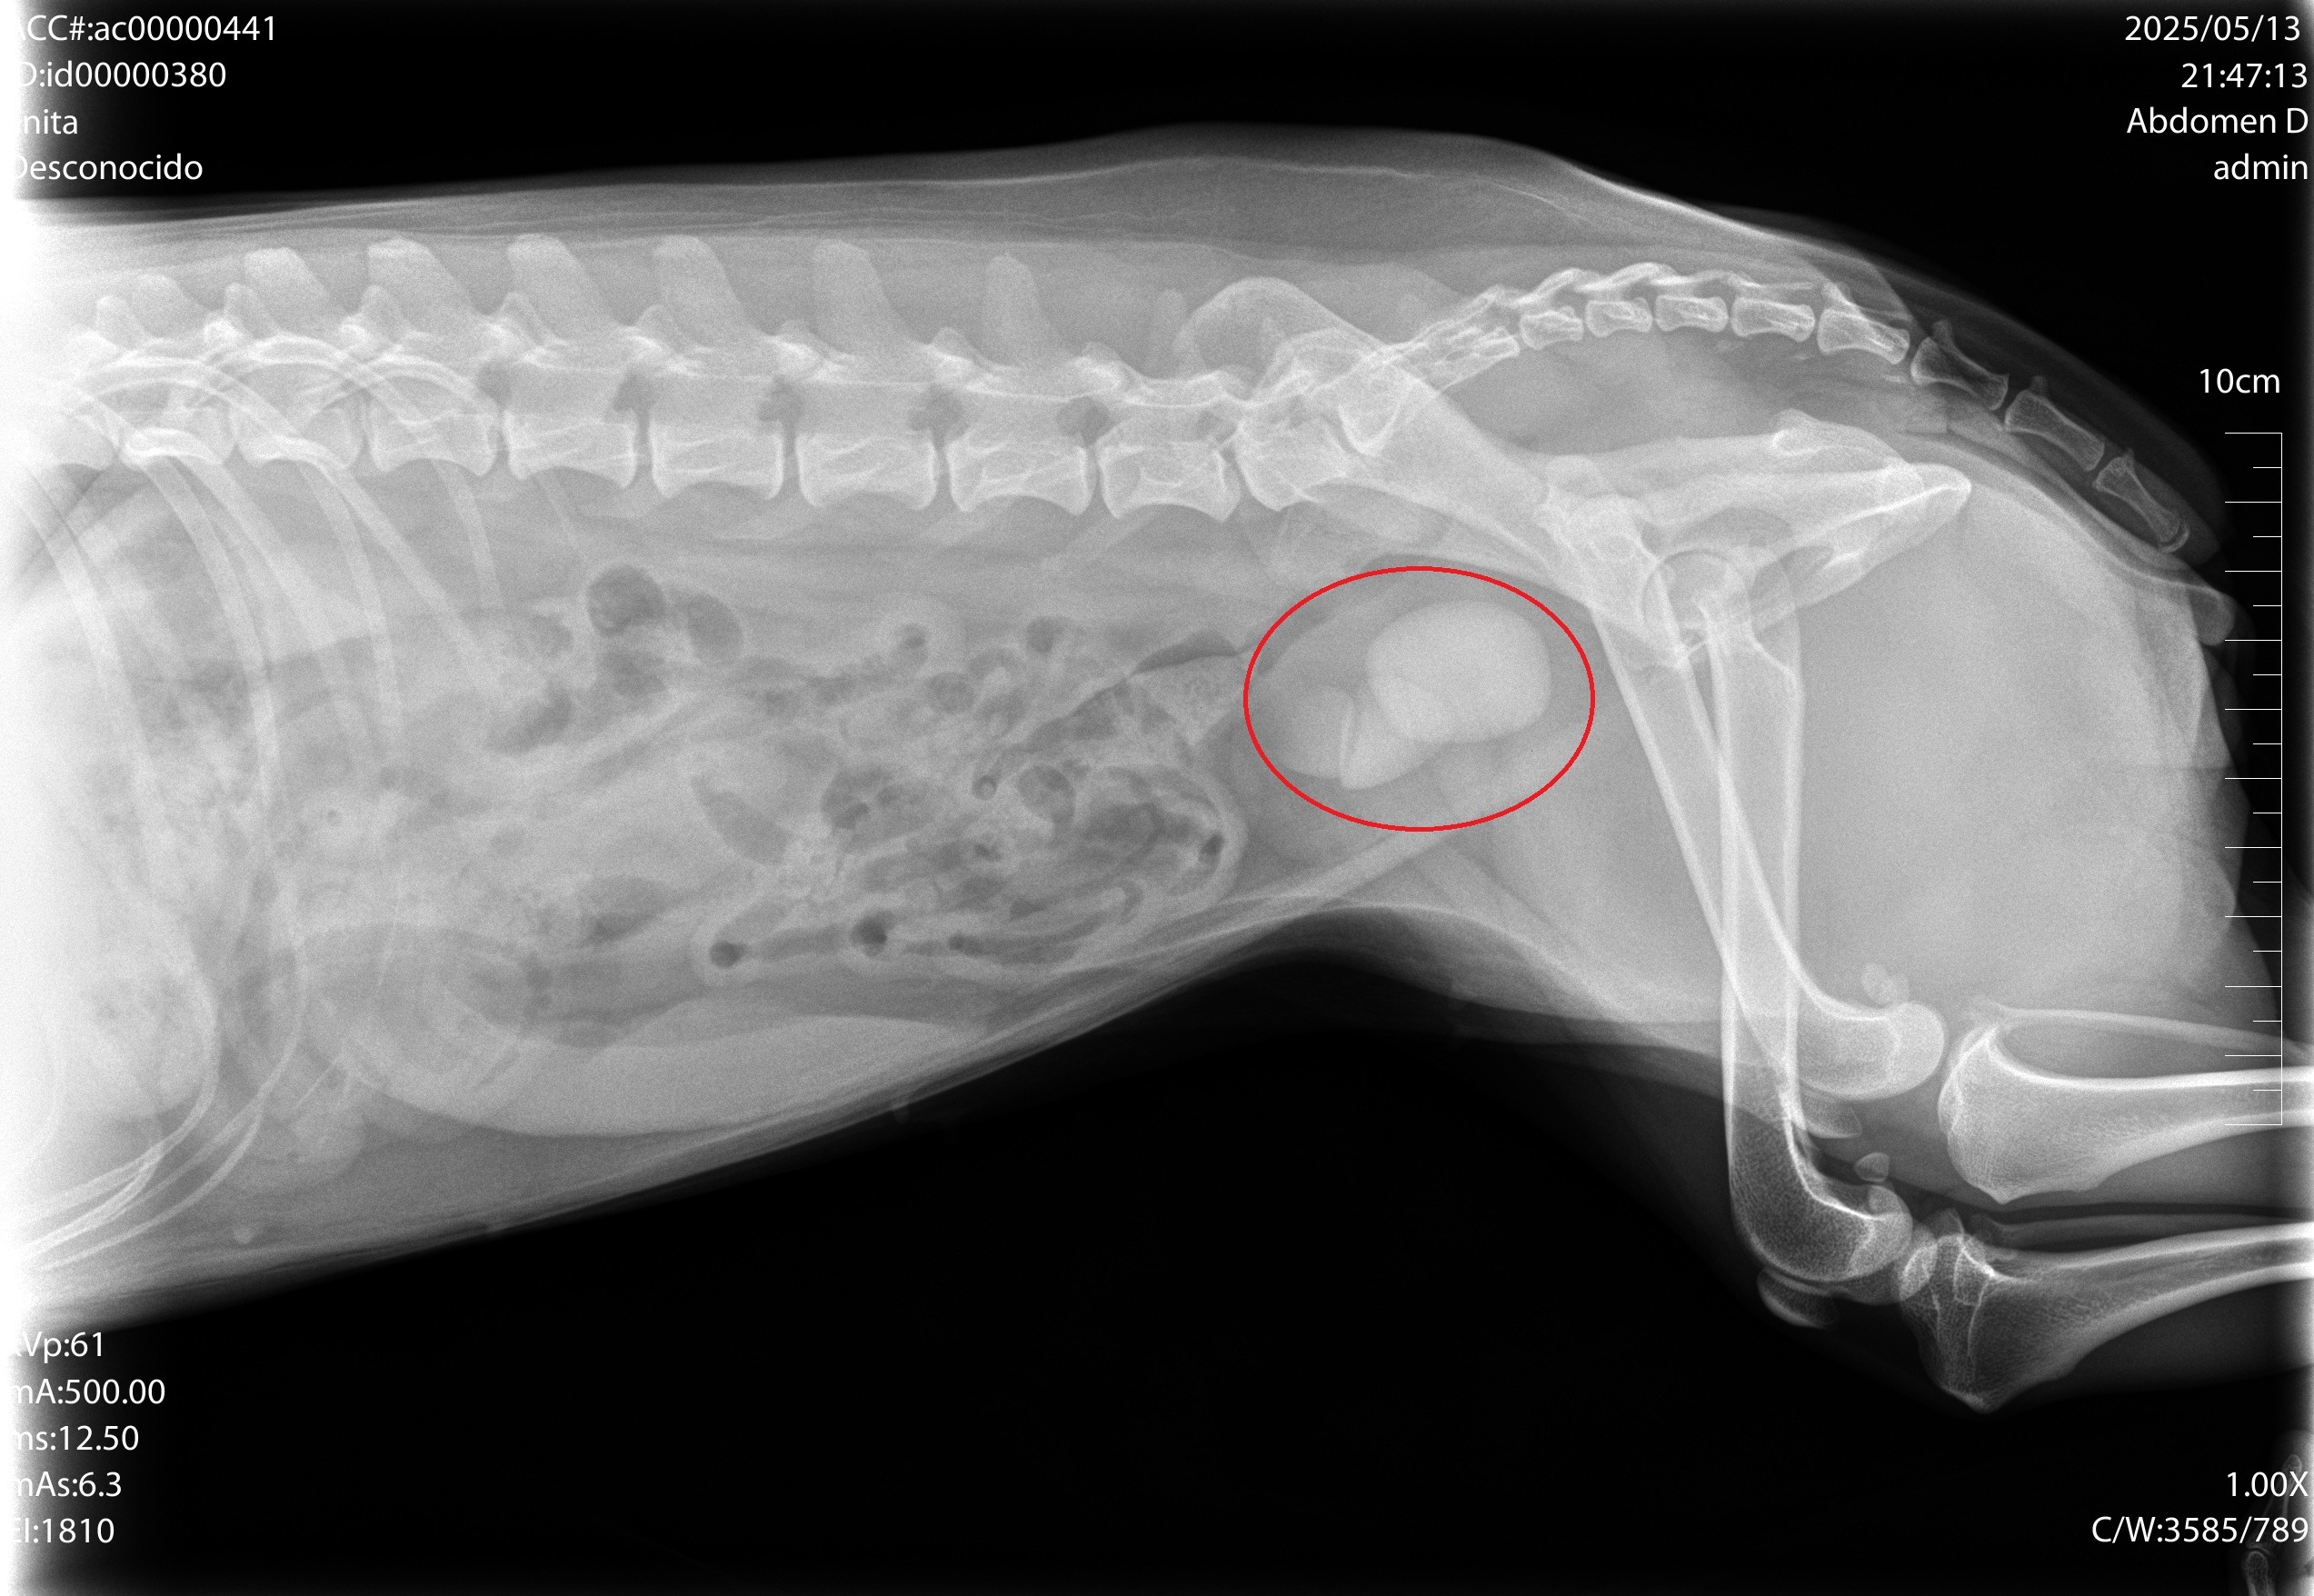

Lamentablemente, desde hace dos meses está muy enferma. Le han detectado tres cálculos en la vejiga y ahora orina sangre constantemente, lo que nos tiene profundamente angustiados. El veterinario nos ha informado que necesita una operación (CISTOTOMIA) urgente para poder recuperarse, y el coste del procedimiento ronda los 1.000 euros, la cotización de la clínica no incluye otros gastos como hospitalización, medicamentos post operatorios, exámenes después de cirugía y demás cuidados.